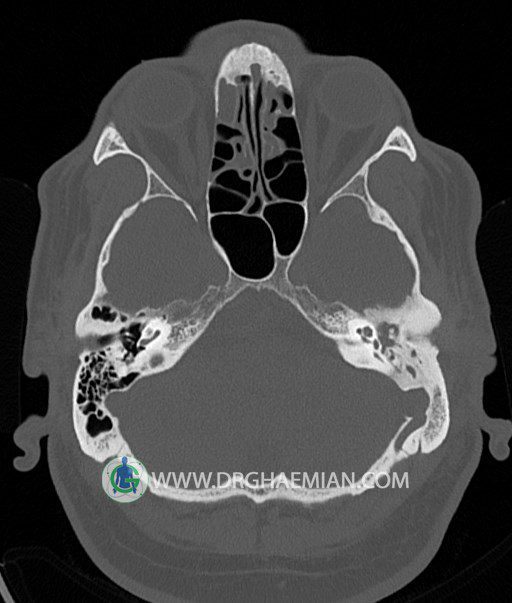

سی تی اسکن گوش داخلی به رادیولوژیست اجازه می دهد تا سطوح مختلف، یا اسلایس هایی از استخوان های که از جمجه به گوش می روند را از طریق امواج ایکس چرخشی مشاهده کند. در این کیس اودیت مدیا، ماستوئیدیت مزمن، اوتیت خارجی، انحراف سپتوم بینی، کونکا بولوزا و افزایش ضخامت سینوس ها مشاهده می شود.

در HRCT از استخوان تمپورال با مقاطع آگزيال ، ساژيتال و کرونال ظريف ( 0.6 mm ) :

– اپاسيتي گوش مياني چپ ناشي از وجود دانسيته نسج نرمي دراطراف استخوانچه ها همراه با اروژن اسکوتوم و

استخوانچه ها بدون جابجايي در رديف استخوانچه ها مشهود است که مطرح کننده اوتيت مديا همراه با نشانه

هاي مشکوک به کولستئاتوم مي باشد .

– اپاسيتي و اسکلروزيس ماستوئيد چپ نشانه ماستوئيديت مزمن

– اپاسيتي کانال گوش خارجي ناشي از دانسيتي نسج نرمي مطرح کننده external otitis